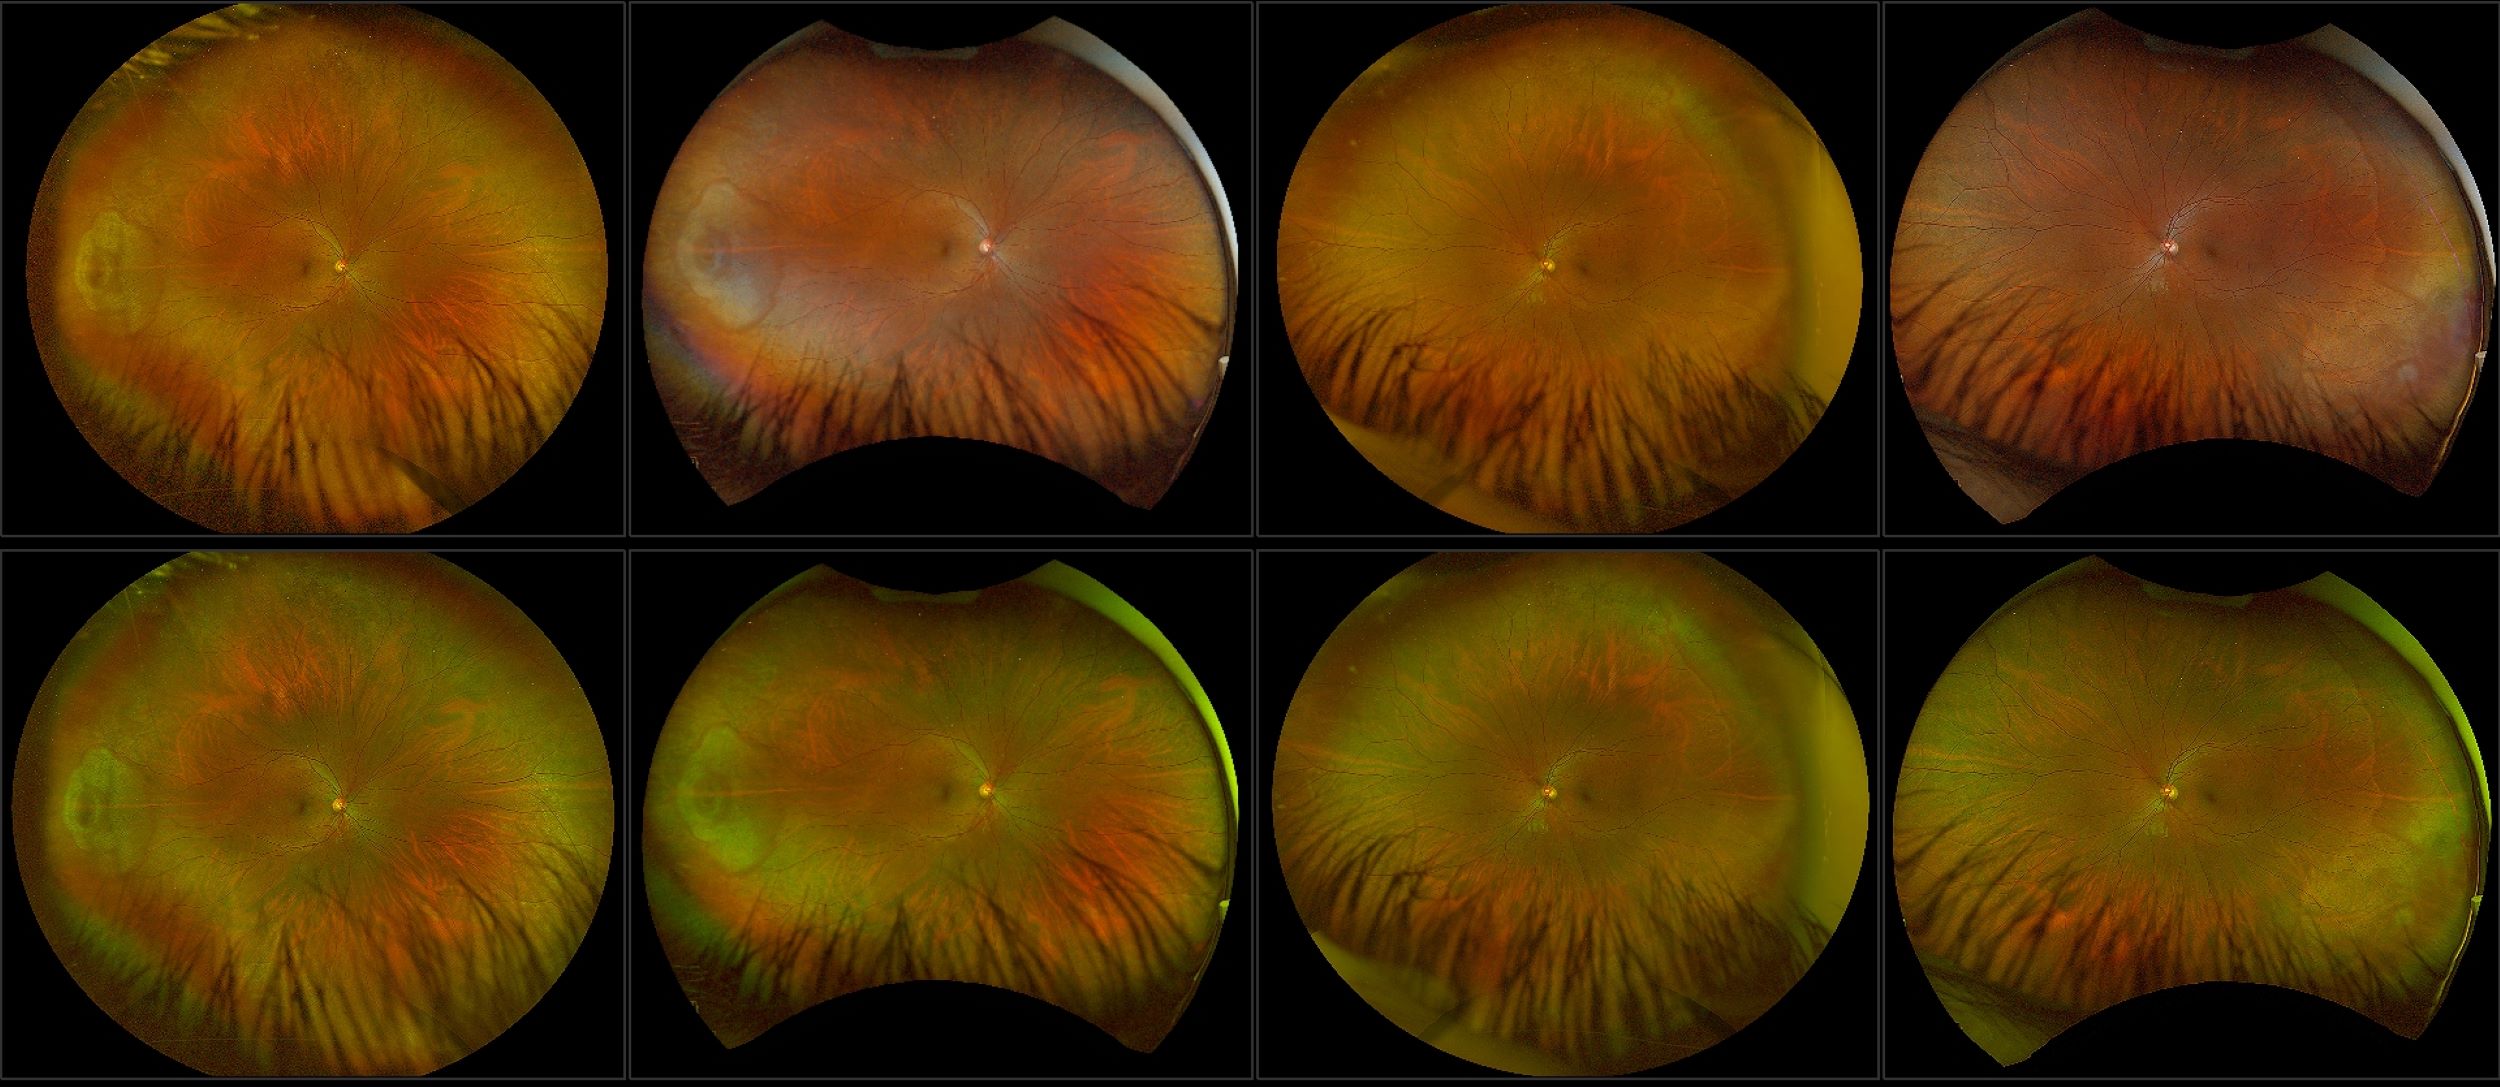

California - Large Pars Plana Cysts - Steered, RG

Pars plana cysts are a common peripheral retinal pathology that do not raise much clinical concern. They do not affect the central vision and observation alone is typically recommended. Pars plana cysts are something to be considered when peripheral retinal elevation is noted on routine exam.